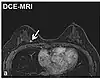

Dynamic contrast enhancedDCEMeasures changes over time in the shortening of the spin–lattice relaxation (T1) induced by a gadolinium contrast bolus.[76] Faster Gd contrast uptake along with other features is suggestive of malignancy (pictured).[77]